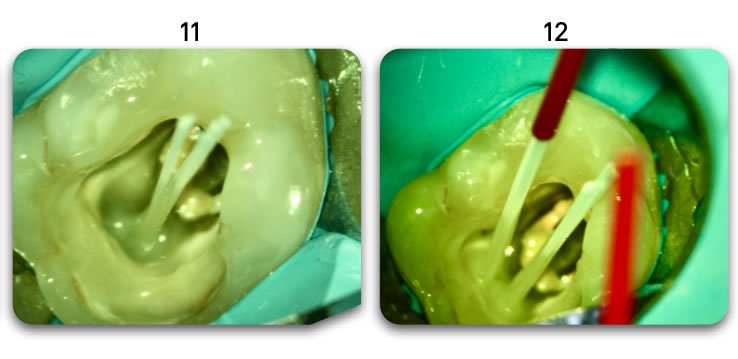

Template for x-rays

Biolight® DRILL-FREE posts are available in bundles of 4, 6, 9 and 12 strands. The post size is selected based on the width of the canal at the coronal area. Depending upon the canal width at the apical stop, a certain number of strands must be pushed to the stop. Both of the measurements are made with the assistance of a radiograph and the template that is included in the TRAINING KIT.